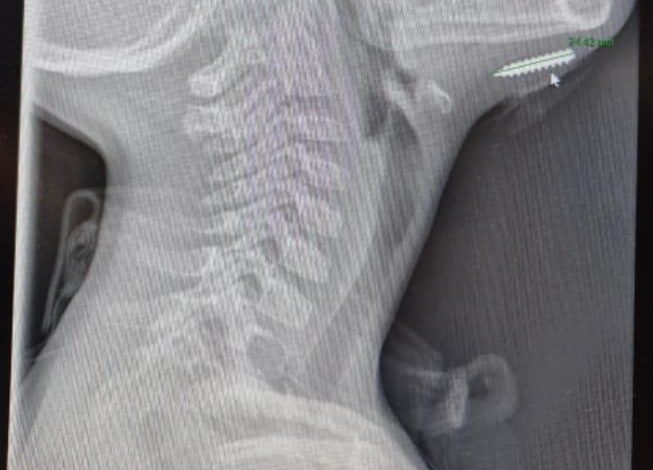

الدكتور بشير نصر الله، أخصائي طب الطوارئ للأطفال، أجرى فحصًا بالموجات فوق الصوتية (POCUS) بجانب سرير الطفل، ليتبيّن وجود جسم غريب عالق في عمق الأنسجة. وبعد تصوير بالأشعة السينية، اتضح أنّ المفاجأة كانت برغيًا معدنيًا بطول نحو سنتيمترين مغروسًا داخل الذقن.